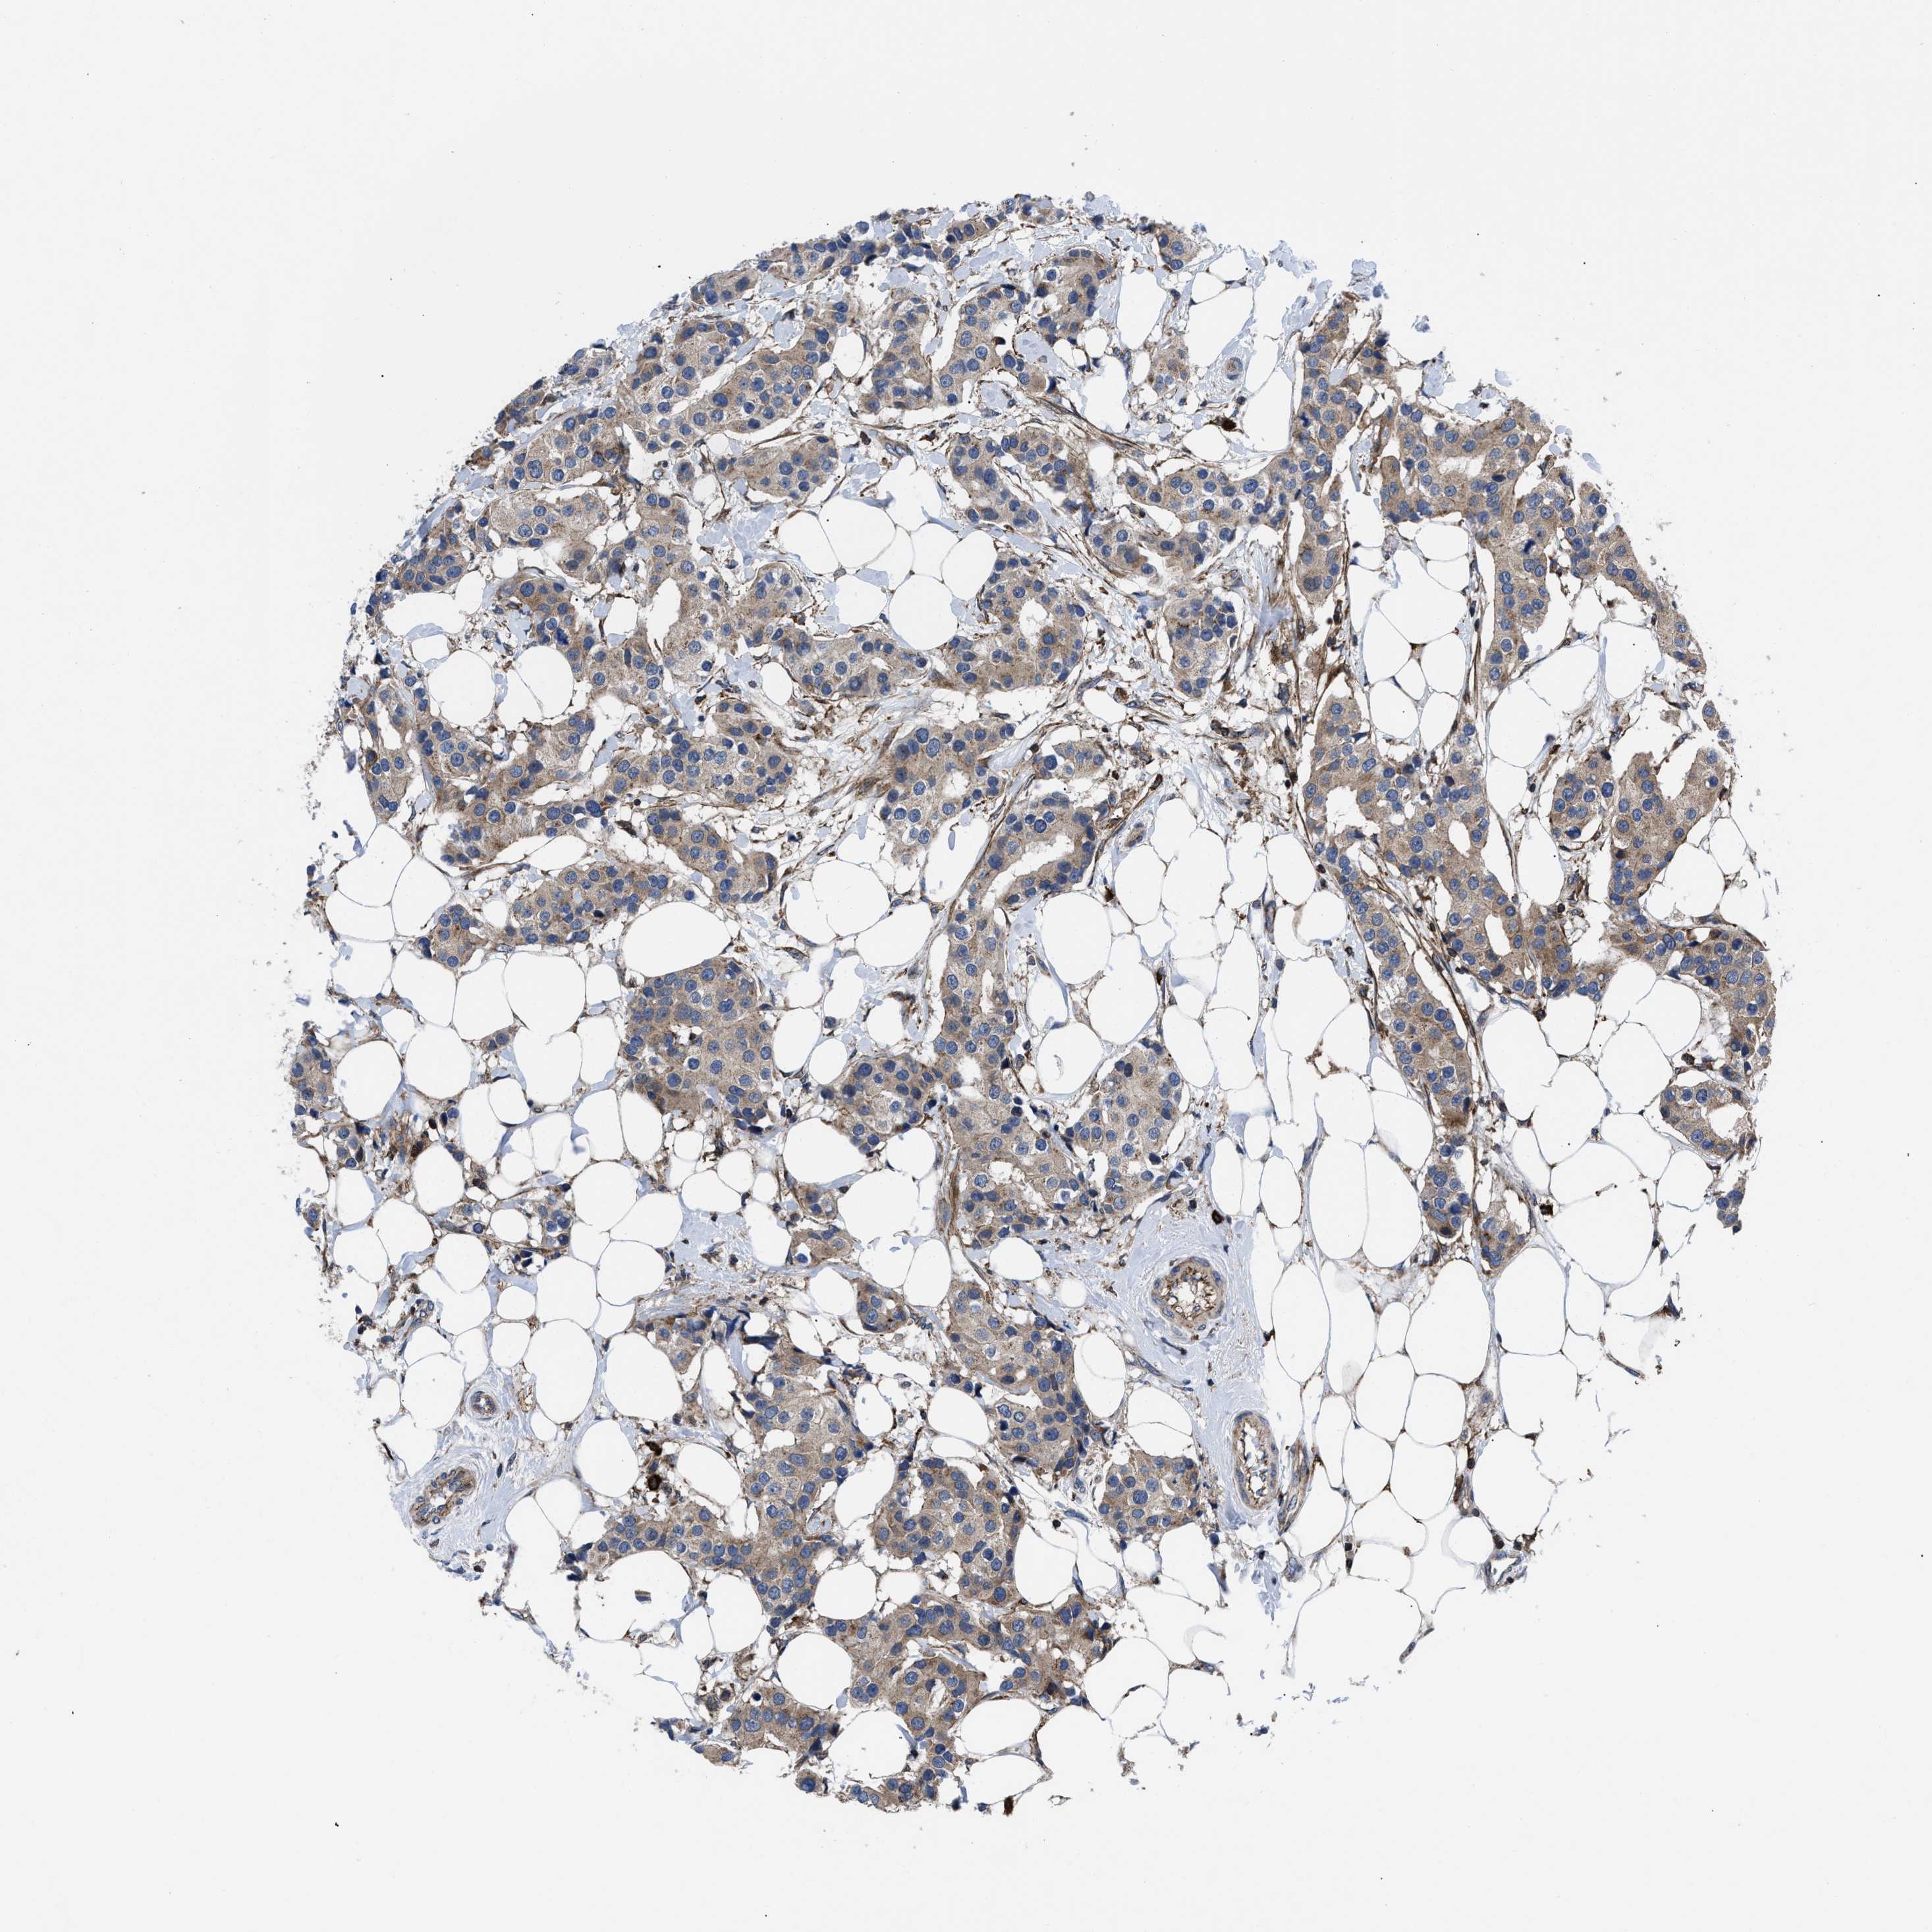

BRCA TCGA BRCA VALIDATION PROTEIN EXPRESSION

ANTIBODIES

AND

VALIDATION